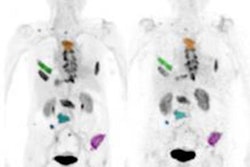

For this retrospective analysis, the researchers collected data from 36 patients who underwent a total of 128 PET scans of the kidneys, liver, lung, and spleen at Amsterdam University Medical Center; Centre Hospitalier Régional at the Universitaire de Lille in Lille, France; and Memorial Sloan Kettering Cancer Center in New York City. The exams were conducted over one to seven days after injection with an appropriate Zr-89-labeled antibody to image their tumors. The four Zr-89-labeled antibodies were Zr-89 obinutuzumab, Zr-89 cetuximab, Zr-89 huJ591, and Zr-89 trastuzumab. Nonspecific uptake was defined as activity measured in tissues without known target expression, which is to say, normal tissue.

Jauw and colleagues were able to quantify nonspecific uptake of monoclonal antibodies in normal tissue using Zr-89 immuno-PET at multiple time points during the seven-day period. By having this data from antibody distribution to normal tissues and tumors, the researchers believe they can enhance their knowledge of which drugs will be effective and, conversely, which drugs are likely to cause toxicity in cancer patients.

"Usually, Zr-89 immuno-PET scans are analyzed at a single time point, representing the sum of all physiologic components of antibody distribution, being either target-specific or nonspecific," the researchers explained. "This study showed how the various physiologic components of antibody distribution contribute to the measured SUV."